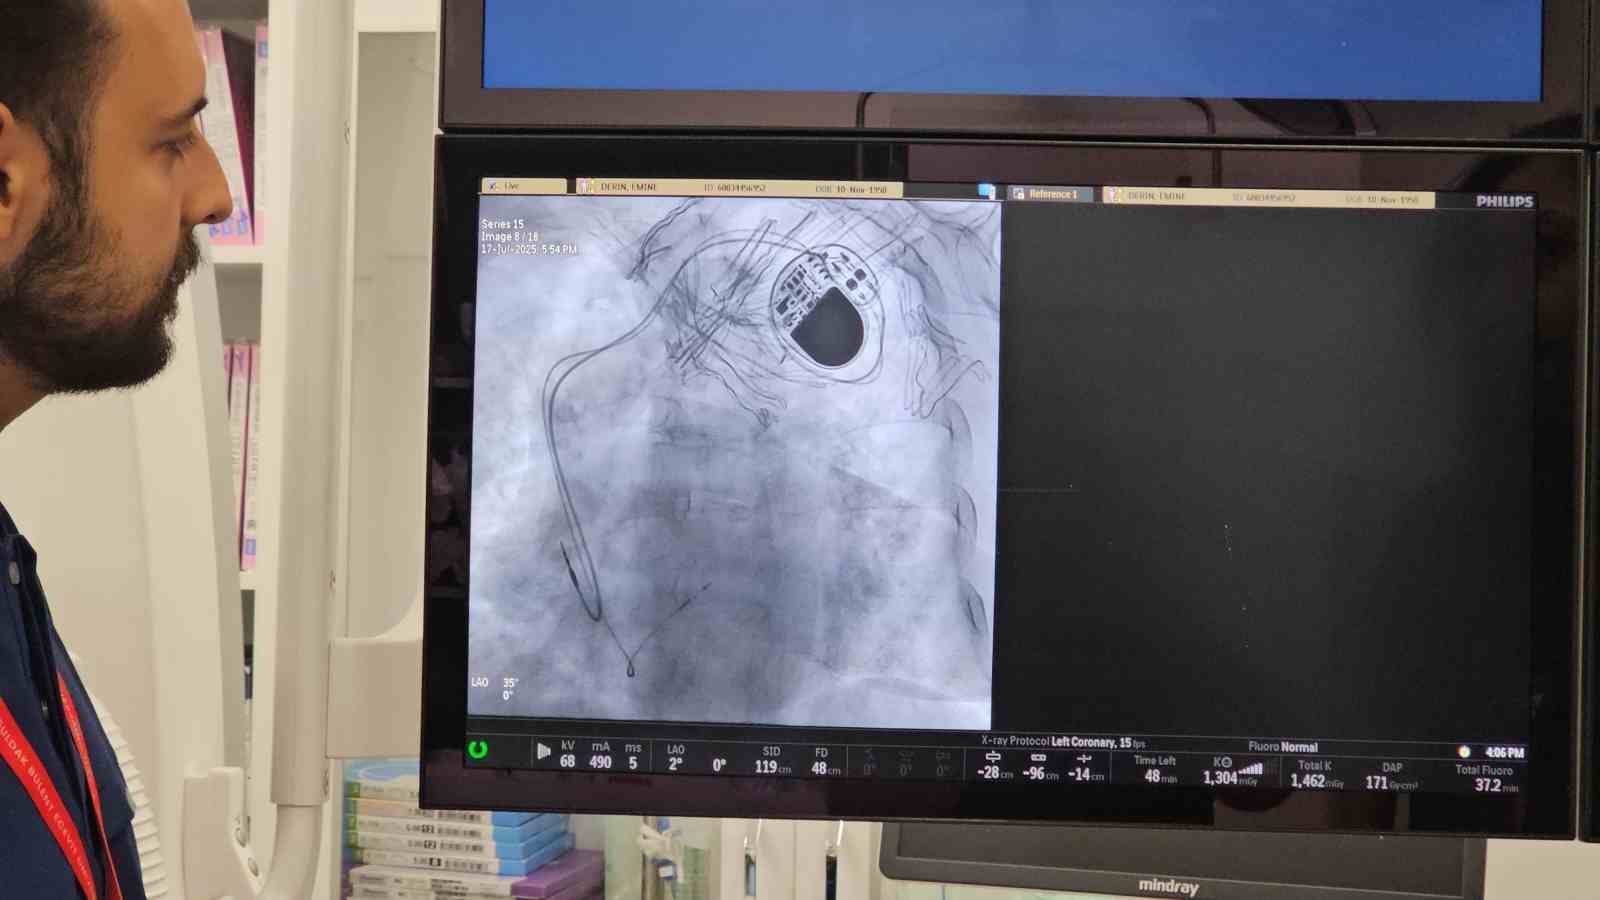

Zonguldak Bülent Ecevit Üniversitesi (BEUN) Tıp Fakültesi Kardiyoloji Ana Bilim Dalı’nda; ritim bozukluğu yaşayan hastalar için yakma (ablasyon) ve dondurma (kriyoablasyon) işlemleri uygulanmaya başlandı.

Kardiyoloji Ana Bilim Dalı Doktor Öğretim Üyesi İlke Erbay, bölgede önemli bir eksikliği giderdiklerini belirterek, "Ritim bozukluğu olan hastalarda yakma ve dondurma işlemlerini kapsayan bir yöntemdir. Bunun daha öncesinde bölgemizde kısa bir süre içerisinde de gerçekleştirilmiş olup şu anda tekrardan devamlılığını sağlayacağız" dedi.

Erbay, bölgede birçok aritmi hastasının İstanbul, Ankara ve İzmir gibi büyük merkezlere sevk edildiğini belirterek, "Bu ritim bozukluğu hastalarımızda özellikle ölümcül ritim bozukluğu olan ya da hayat kalitesini düşüren ritim bozukluğu olan hastalarımızda yakma işlemleri ve dondurma işlemlerini kurumumuzda ve bölgemize hizmeti sunmaya başladık. Zaten vakalarımıza hızlı bir şekilde başladık" ifadelerini kullandı.